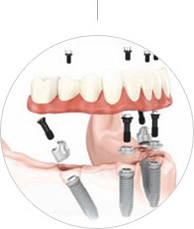

殷先生的牙齿状况比较特殊:上排牙骨比下排本身就窄,上牙槽骨还缺牙30多年,废用性萎缩非常严重。此前预约了很多口腔医院,普通的种植牙技术恐怕很难实现上面半口种植,并且在咬合和美观度方面也无法达到预期效果!郑苍尚院长综合考虑目前牙齿具体情况为殷先生推荐all-on-4(种植4颗即能恢复半口牙)手术方案......

由于严重的牙周病,他的上半口牙齿全掉光了,下牙也缺了一颗,硬的、粘的、肉类都没法吃。蒋先生在女儿的陪同下到麦芽口腔口腔看牙,接受了麦芽口腔的即刻负重种植牙手术,通过创新性地应用拱形受力原理,仅植入4颗种植体,达到12~14颗牙的修复效果,马上戴上临时牙冠,恢复咀嚼......